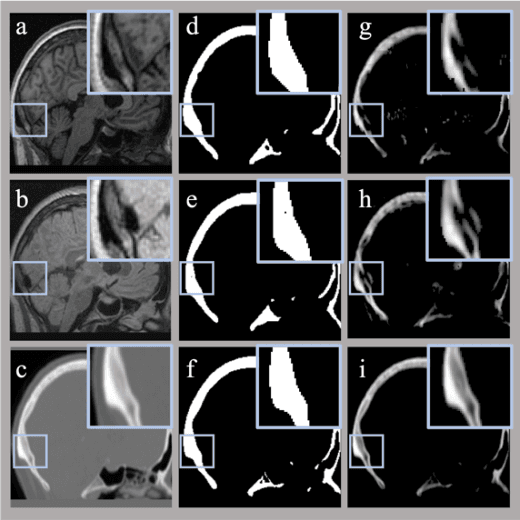

Abstract:Image segmentation, real-value prediction, and cross-modal translation are critical challenges in medical imaging. In this study, we propose a versatile multi-task neural network framework, based on an enhanced Transformer U-Net architecture, capable of simultaneously, selectively, and adaptively addressing these medical image tasks. Validation is performed on a public repository of human brain MR and CT images. We decompose the traditional problem of synthesizing CT images into distinct subtasks, which include skull segmentation, Hounsfield unit (HU) value prediction, and image sequential reconstruction. To enhance the framework's versatility in handling multi-modal data, we expand the model with multiple image channels. Comparisons between synthesized CT images derived from T1-weighted and T2-Flair images were conducted, evaluating the model's capability to integrate multi-modal information from both morphological and pixel value perspectives.